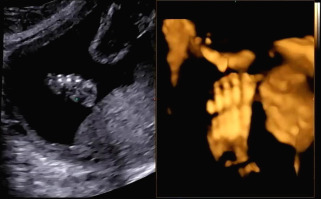

입체 초음파 또한 복부초음파처럼 침대에 누워 태아의 상태를 확인하는데 정밀검사처럼 태아의 손, 발뿐 아니라 얼굴 생김새까지 확인이 가능하다.

바른 자세로 누워 초음파를 시작했다. 손가락, 발가락뿐 아니라 양측 귀까지 입체 초음파를 통해 확인하고 태아의 얼굴 생김새를 확인했다. 일반 초음파로 확인할 때와 다르게 입체적으로 보이는 태아의 모습에 신기했다.

다른 부분을 확인하고 태아의 얼굴을 보기 위해 초음파를 시작하는데 아기가 자궁벽을 향해 얼굴을 붙이고 있어서 초음파에서 얼굴을 보기 힘들었다. 입체 초음파로 생김새를 정확히 보기 위해서는 태아가 양수가 많이 있는 방향으로 얼굴을 가리지 않아야 한다. 햇님이는 벽에 얼굴을 붙인 것뿐 아니라 손으로 얼굴을 가려서 더욱 보기가 힘들었다. 사실 입체 초음파를 보기 전 일반 초음파를 확인할 때 얼굴을 보기 힘들었어서 이번에도 어려울 거라고 예상은 했었다. 그래서 초음파를 확인하는 선생님이 나의 배를 열심히 흔들었다. 태아가 양수의 흔들림에 자세를 바꾸기를 바라며 나의 배를 흔들고 눌렀는데 초음파에서 얼굴 정면을 볼 수 없었다.